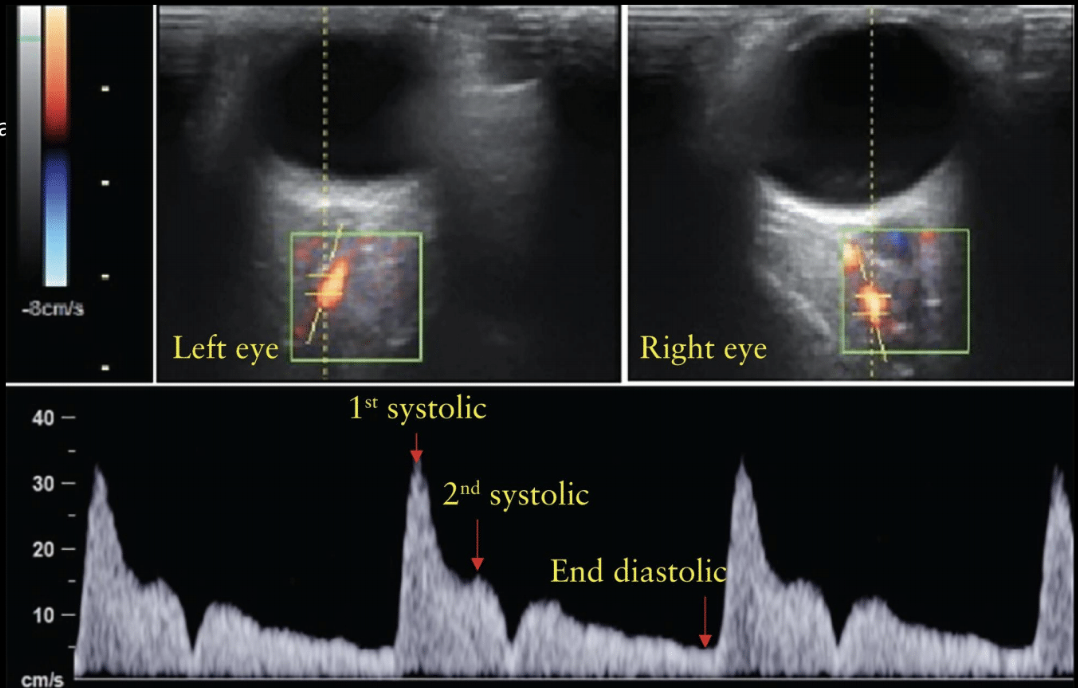

16

Q

A

x = tiempo (segundos)

y = velocidad (cm)

positivo = por encima de la línea

negativo = por debajo de la línea

Usos del doppler en arteria oftálmica

Embarazadas, para evaluar riesgo de preeclampsia

Riesgos en pacientes con falla cardiaca